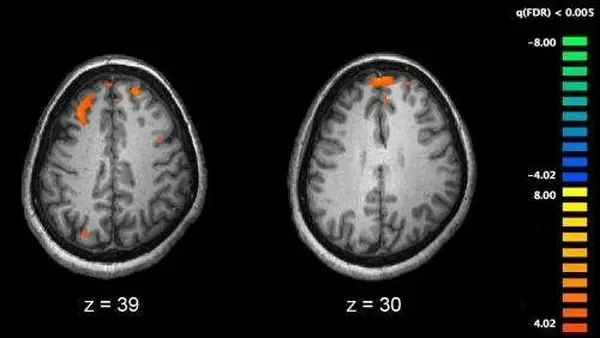

به گزارش  فیز، یک گروه پژوهشی از "دانشگاه کالیفرنیای جنوبی" (USC)، 150 پروتئین موثر بر فعالیت سلول و رشد مغز را شناسایی کرده است که در اختلالات روانی از جمله اسکیزوفرنی، اختلال دوقطبی و افسردگی نقش دارد.

ارتباط ژن DISC1 با اسکیزوفرنی، تقریبا 20 سال پیش اعلام شد. این ژن، شبکه‌ای از سیگنال‌ها را در سرتاسر سلول هدایت می‌کند که در شکل گیری اسکیزوفرنی نقش دارند. به گفته دانشمندان، خطا در واکنش‌های شیمیایی نیز در بروز این بیماری موثر هستند اما شناسایی پروتئین‌هایی که DISC1، توانایی تنظیم آنها را دارد، به سختی انجام می‌شود.

این موضوع، گروه پژوهشی دانشگاه کالیفرنیای جنوبی را به انجام دادن این پژوهش ترغیب کرد. آنها با استفاده از سلول‌های بنیادی، آزمایش‌هایی انجام دادند که در آن، زیستگاه DISC1 شبیه‌سازی شده بود. سپس، برای گذاشتن تگ مولکولی روی DISC1، از اصلاح ژن استفاده کردند. این کار، امکان خارج کردن DISC1 را از سلول‌های مغز و شناسایی پروتئین‌های مربوط فراهم کرد.

ممکن است شناسایی پروتئین‌های مرتبط با DISC1 در سلول‌های مغز، به درک چگونگی ارتباط عوامل خطرناک بیماری‌های روانی با عملکرد مولکولی خاص، منجر می‌شود. این کشف به پژوهشگران فرصت می‌دهد فرآیندهای خاصی را تعیین کنند که در بیماران مبتلا به اختلالات روانی خاص، متفاوت است.